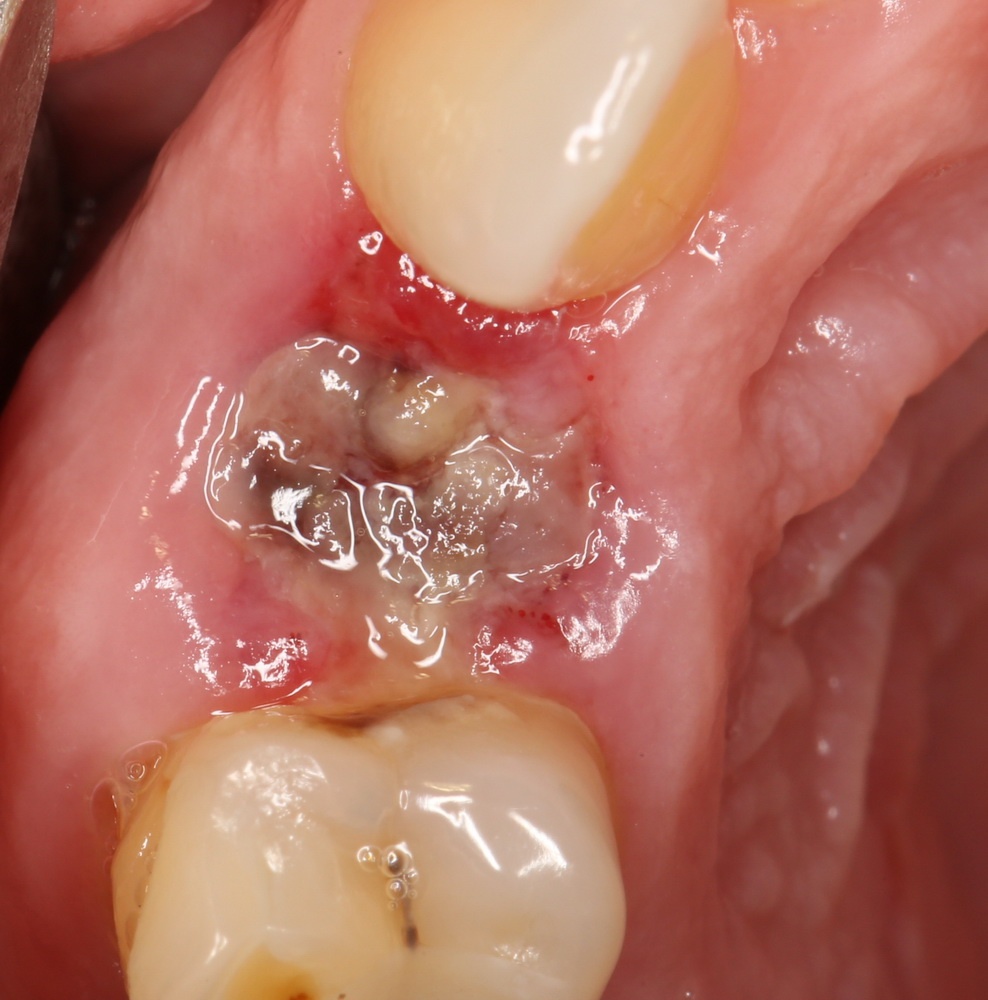

Через день-два лунка удаленного зуба выглядит следующим образом:

Постепенно кровяной сгусток из темно-бордового превращается в желтовато-белый. Связано это с тем, что красная его часть (эритроциты и гемоглобин) вымываются ротовой жидкостью, остается только фибриновый каркас. Многие пациенты путают его с гноем, пытаются вычистить. Не нужно этого делать.